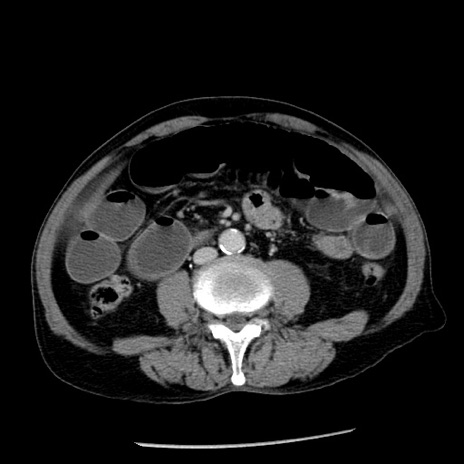

症例26(横断像)

【症例】80歳代男性

【主訴】嘔吐

【現病歴】昨晩2回嘔吐あり、今朝になっても嘔吐あり。来院。

【既往歴】胃潰瘍

【身体所見】意識清明、BT 37.6℃、BP 166/95mmHg、HR 100bpm、SpO2 97%、腹部:平坦・軟、腸蠕動音聴取良好、圧痛なし。

【データ】WBC 21900、CRP 1.46